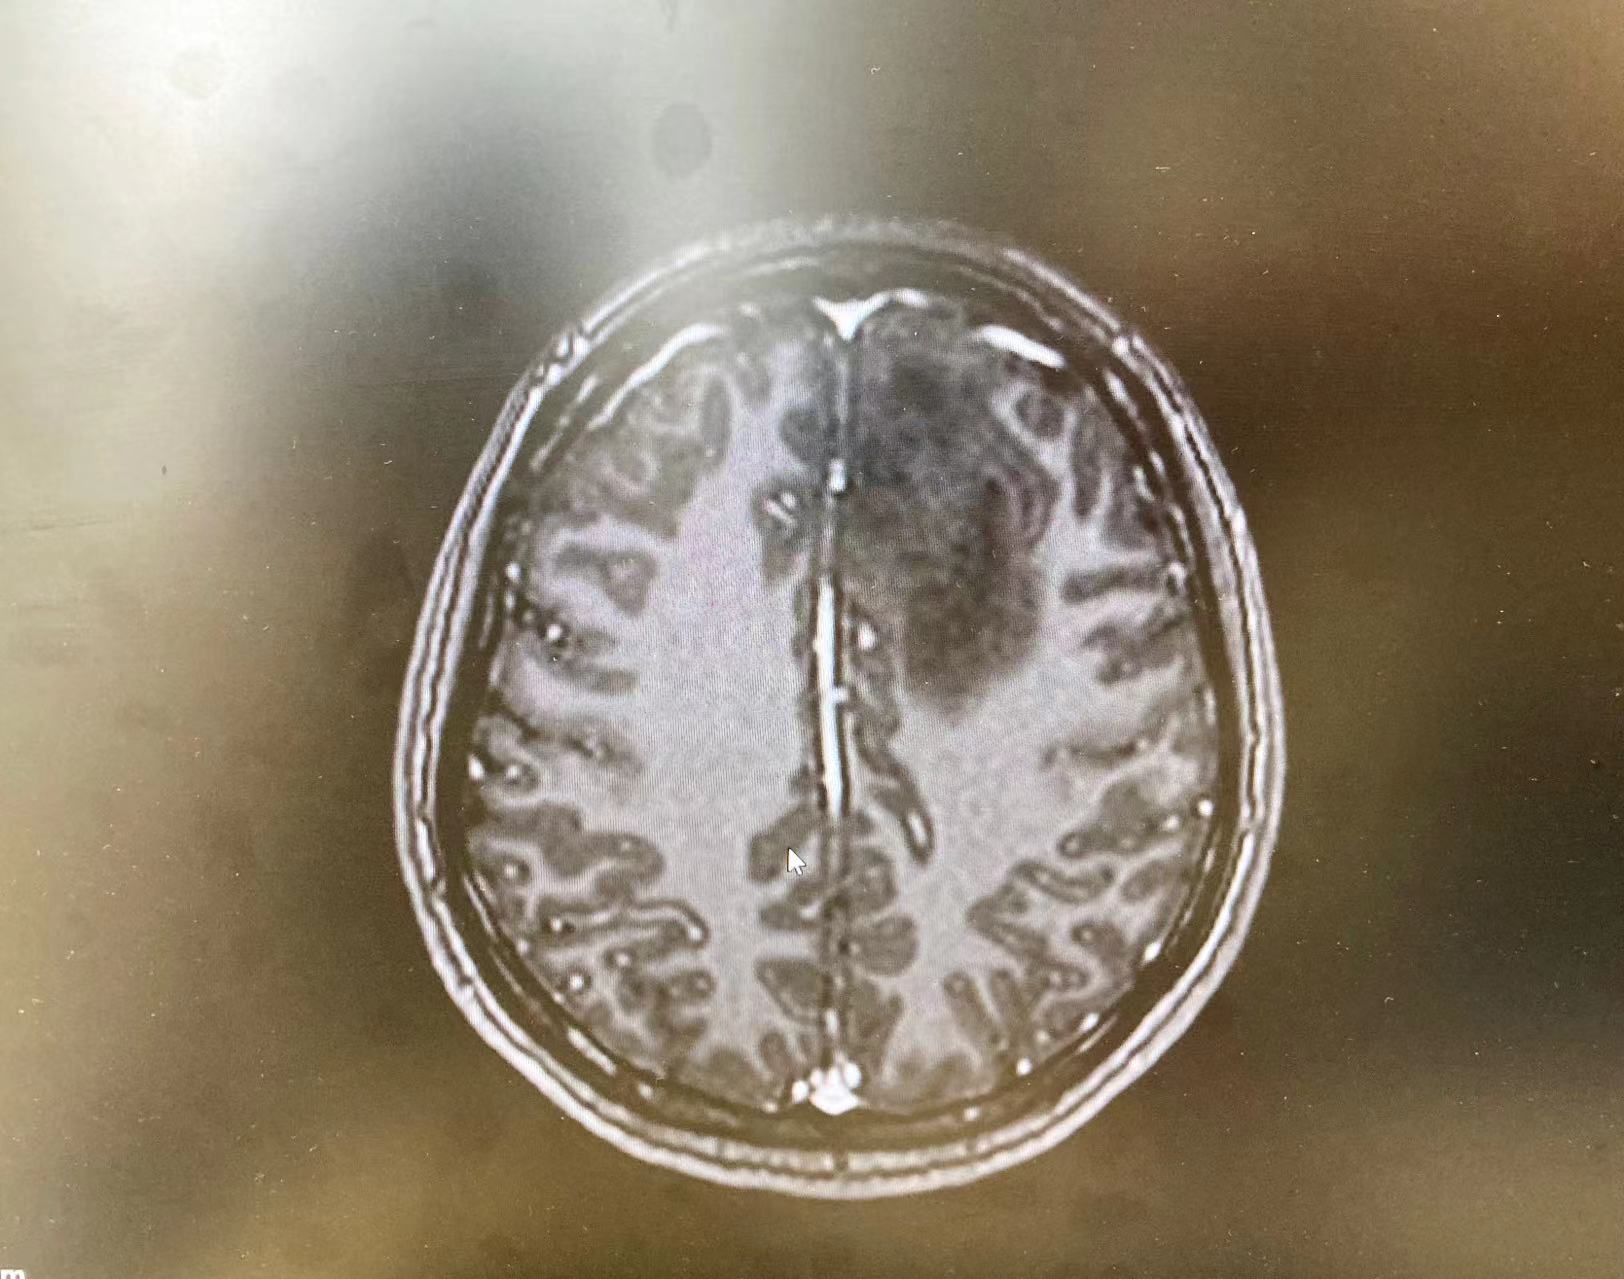

7月中旬,徐女士在午睡时突然持续尖叫,随即意识丧失,呼之不应,双眼上视,口吐白沫,四肢抽搐不止,持续数分钟后才有所好转,家人非常担心。经核磁共振结果和一系列影像检查提示,徐女士左侧颅内占位性病变,诊断为脑胶质瘤,医生建议手术治疗。

MR影像提示胶质瘤。